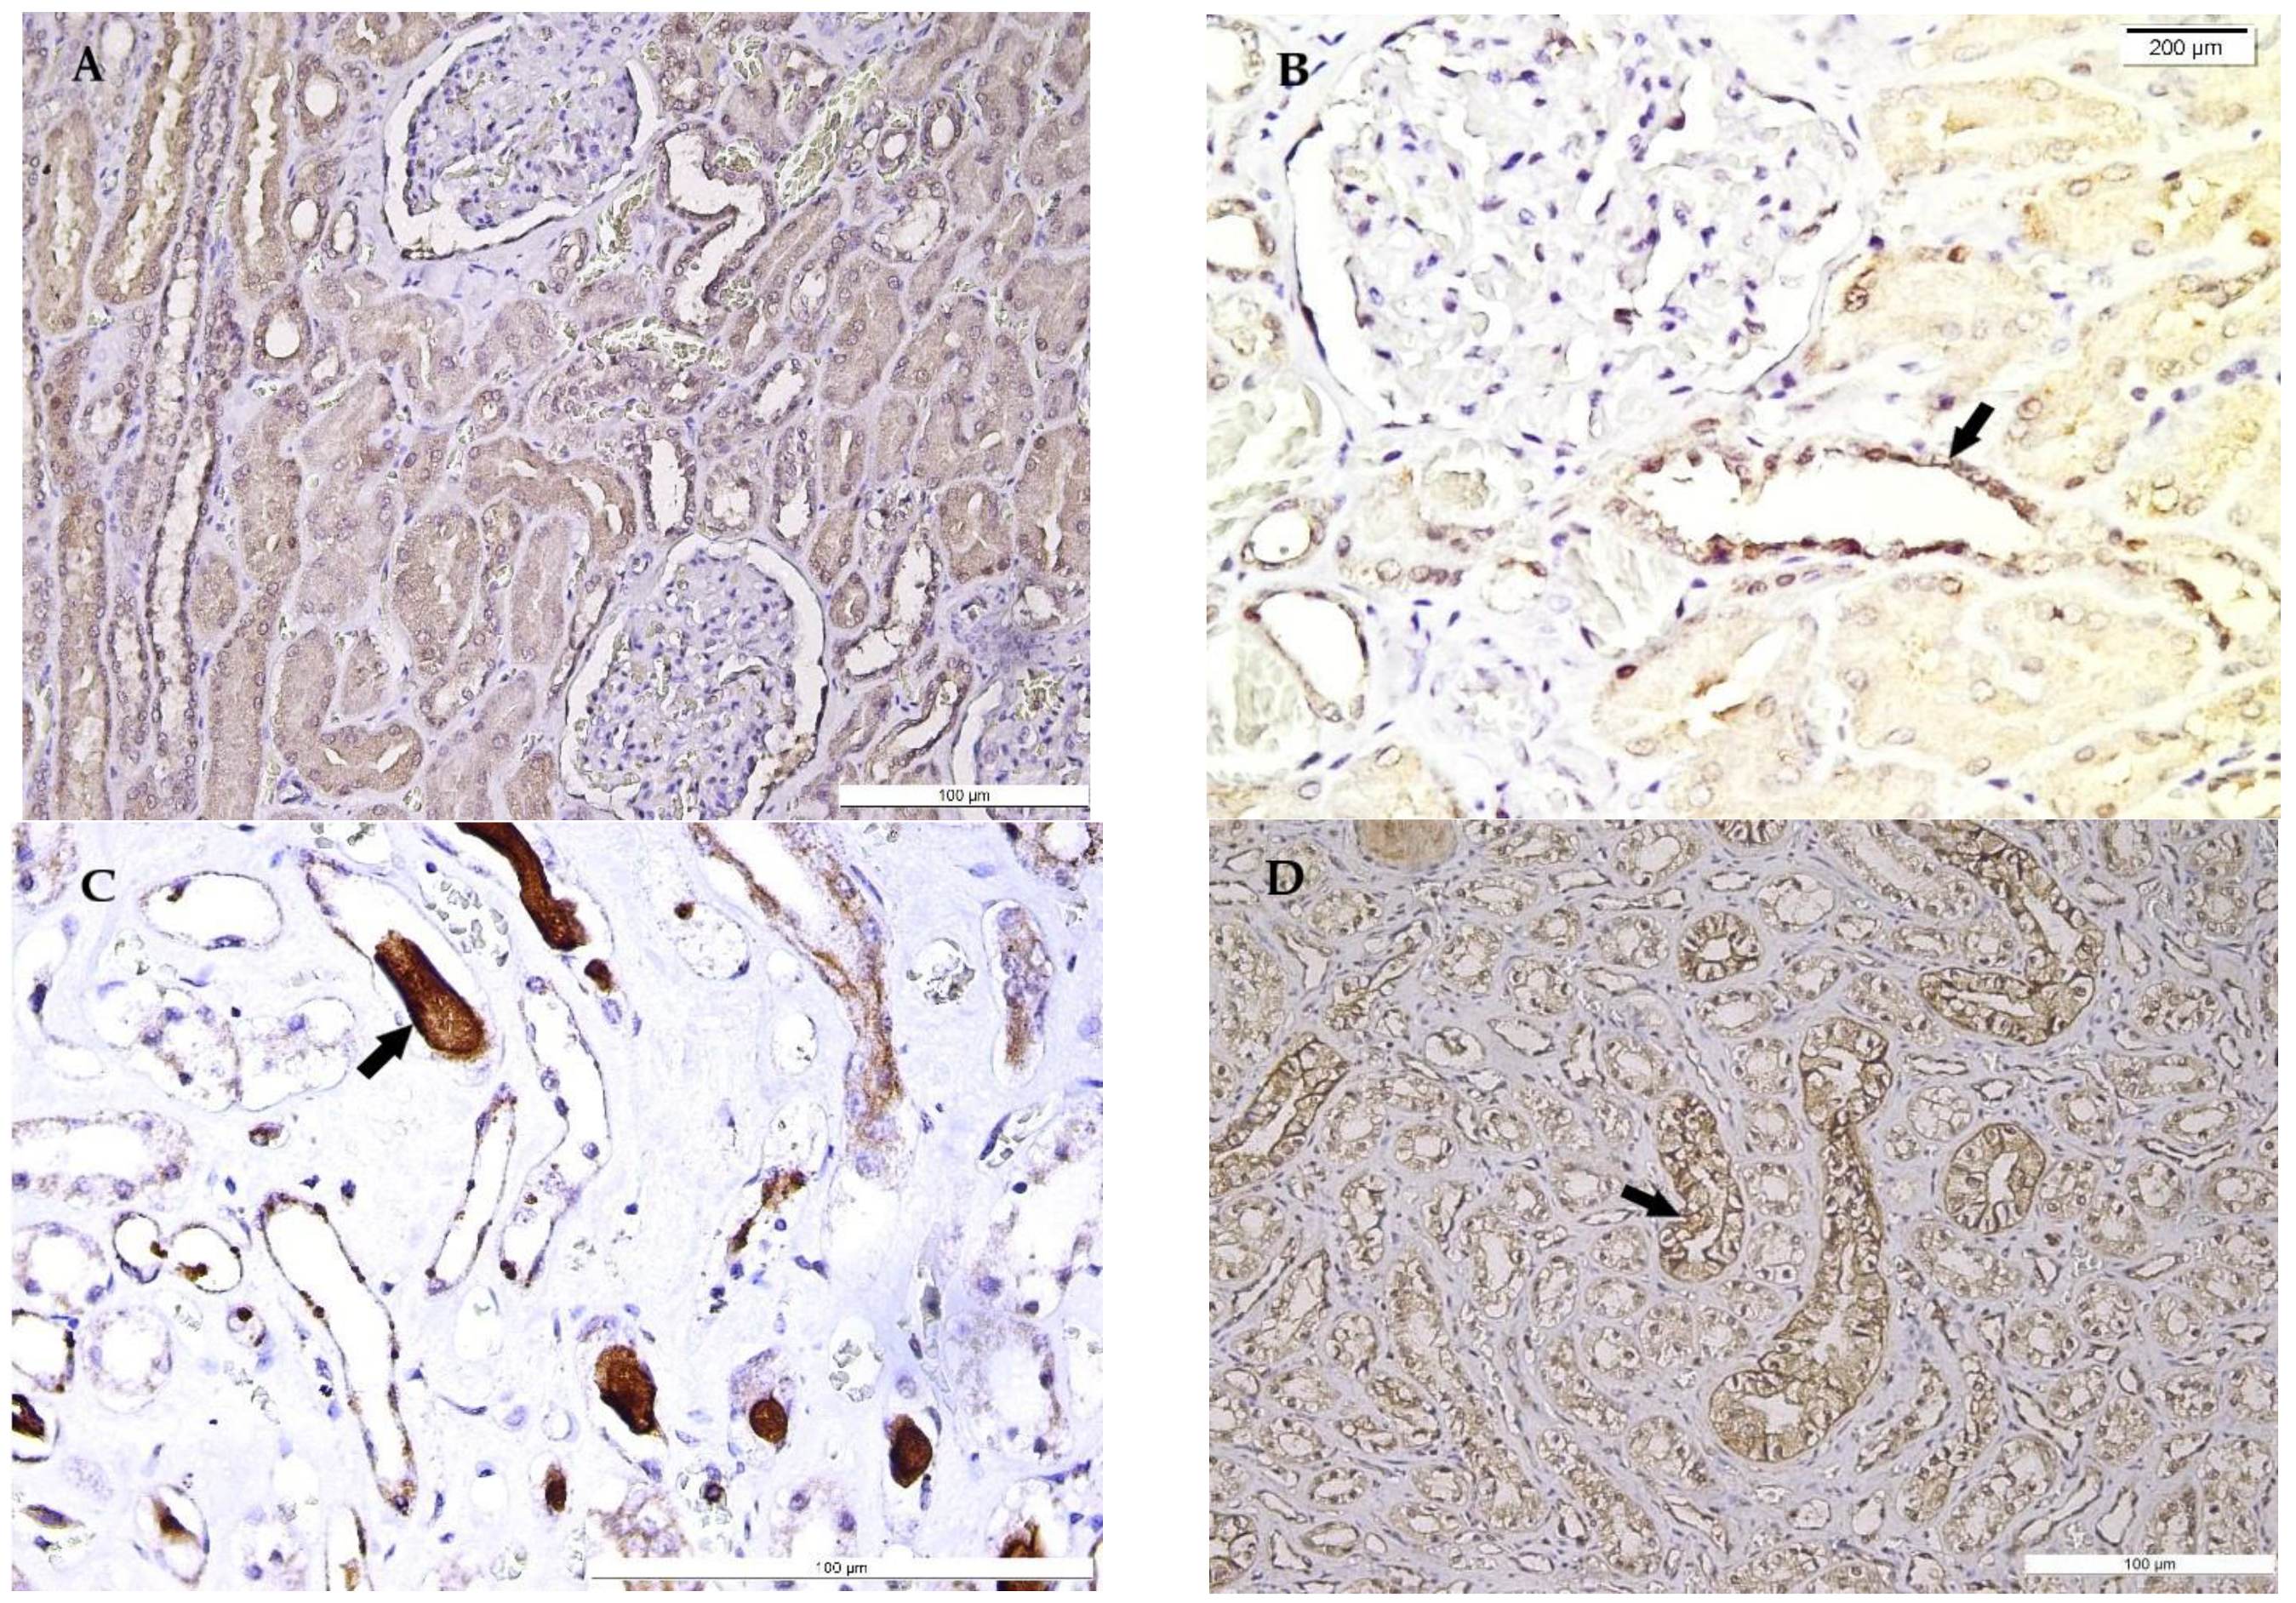

Figure 4.

Ubiquitin (Ub) expression in the kidney in hypothermia cases. (A) General view of Ub expression in renal corpuscles and proximal and distal convoluted tubules. (B) Ub strong expression in renal corpuscle and distal convoluted tubules (arrow), compared with weak expression in proximal convoluted tubules. (C) Ub expression in distal convoluted and collecting tubules, Henle’s loops, and intratubular casts (arrow). (D) Cytoplasmic and focal membrane Ub expression in renal collecting tubules (arrow) and Henle’s loops epithelium and weak Ub expression in a tubular cast (left top of the image).

Ub membrane positive expression in distal and collecting renal tubules in Henle’s loops, along with the immunopositivity of calyces’ transitional epithelium, have been observed, while weaker immunostaining has been noticed in proximal convoluted tubules. Additionally, the protein-like intratubular casts expressed a variable Ub-positive pattern (Figure 4).

Ub is a member of the heat shock protein family, which may be stimulated by a variety of factors such as mechanical or ischemic stress [14]. Ub’s main function is to repair and eliminate denatured proteins, followed by their transport to the proteolytic system, being extremely useful in the investigation of the physiopathological mechanism by correlations between the survival period of time and the cause of death [14,34]. Its immunoexpression has been studied in different circumstances of death, such as arson, cerebral lesions, asphyxiation, and hypoxia, with very limited studies in hypothermia [34,35,36]. Literature data have reported a close correlation between the thermal aggression intensity and Ub-proteasome pathway activation, exhibited in renal tissue by an increased Ub expression in distal convoluted and collecting tubules, due to the thermal-induced rhabdomyolysis of cardiac muscle cells [34], findings which have been also observed in our study. Moreover, Henle’s loop Ub-positive expression has been identified in our study group.

Supplementarily, the cells of proximal convoluted tubules have shown a weaker Ub positivity in our study, as compared to collecting tubules, in agreement with previous reports [34]. Our observations have additionally registered a particular pattern of staining, with focal membrane expression, as well as cytoplasmic staining, in calyces and collecting tubules. Supplementarily, a weak immunopositivity has been also noticed in the intratubular casts of collecting and distal convoluted tubules. Moreover, Ub expression in renal intratubular casts proved to be exclusively observed in distal convoluted and collecting tubules, with a lack of expression in the proximal convoluted tubules in previous studies [34,37], analogous to our findings, suggesting that its mechanism is more active in distal nephron components.

Variable Ub immunoexpression in renal corpuscles, distal convoluted and collecting tubules, Henle’s loops, intratubular casts, and calyx urothelium represents a constant finding in hypothermia. Ub expression may be related to hypoxia and myocytolysis, which may occur in hypothermia.